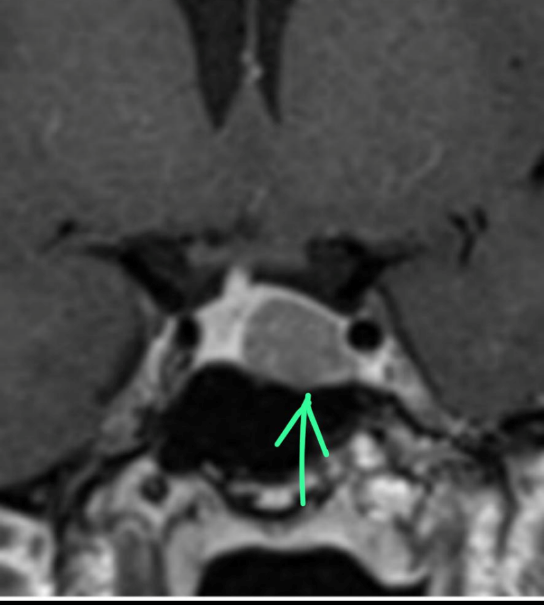

A dynamic contrast-enhanced MRI study highlighted the pituitary microadenoma (Fig 1). Inferior petrosal sinus sampling confirmed an ACTH- secreting pituitary adenoma on the left side (peripheral ACTH – 11.6pg/ml, right IPS- 26.9, left IPS – 44).

Figure 1. Coronal section, T1 weighted post-contrast dynamic sequence image of the pituitary fossa showing the tumour, a rounded region of delayed enhancement (green arrow) compared to the rest of the gland.

She was counselled for total resection of the tumour through an Endoscopic endonasal approach (EEA). EEA was performed through the right paraseptal route with the left rescue flap using the standard endoscope (Fig. 2). ICG was administered and a custom ICG-integrated endoscope was introduced. The tumour was visualized as appearing non-fluorescent compared with the normal pituitary gland (Fig. 3). The adjourning ICA was also visualized (Fig. 4). A soft whitish tumour was resected after capsulotomy. The anterior and posterior lobes were confirmed and remained fluorescent with ICG. Pseudo capsulectomy was added. After total resection, hemostasis was confirmed and the sellar floor was repaired.

Figure 2. Standard endoscopic view of the sellar floor with the bone removed. Inset of the preop coronal MRI image.